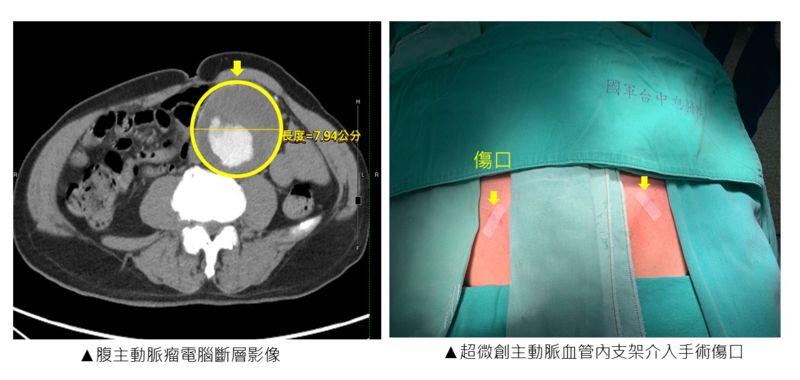

近日有一位70歲蔡先生因嘔吐合併腎臟功能變差,住院進行腹部超聲波檢查,赫然發現原來腹腔內有一個直徑約8厘米的主動脈瘤,經過電腦斷層確認後,蔡先生和太太這才明白,原來這一兩年來蔡先生腹部像心臟一樣搏動的凸起物,其實是一顆巨大的腹主動脈瘤,就像腹部有一顆無聲無息的未爆炸彈!

國軍臺中總醫院心臟血管外科自2017年起,引進了微創主動脈血管內支架手術,造福許多可能需要進行傳統開放式手術的高風險主動脈瘤病患。微創主動脈支架手術是先在腹股溝切開兩道傷口,將導管插入股動脈,接下來輸送主動脈支架到主動脈瘤的位置並展開主動脈支架,展開後的支架將取代主動脈瘤讓血液流通,因此主動脈瘤不會再受血流衝擊,導管自主動脈移除後,將股動脈縫合修補,始才完成手術;而傳統開放式手術則是需要切開腹部一道大約20至30厘米的開口,以利進行主動脈瘤的切除,以及縫合置換上人工血管。

為蔡先生進行微創主動脈血管內支架手術的林敬惟醫師,於本次手術進一步搭配使用經皮血管縫合器系統,利用穿刺的方式取代用手術刀切開傷口,讓兩側腹股溝的傷口從5至7厘米大小縮小至1厘米不到!如此超微創的傷口讓蔡先生術後幾乎感覺不到疼痛,覺得非常驚奇,術後恢復也十分迅速。